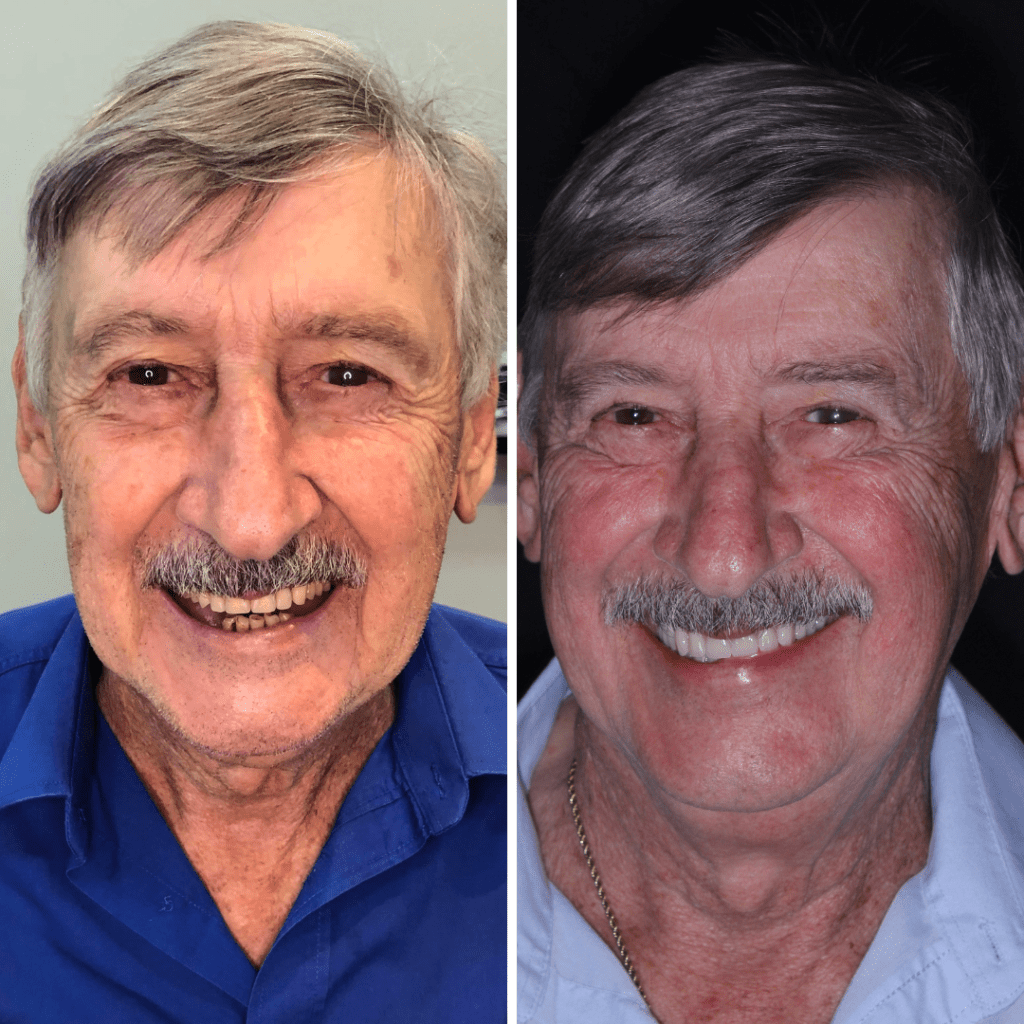

É uma dentadura totalmente fixa sobre implantes e é a prótese que mais fica próxima da sensação de dentes naturais. Ela não é removível, fica fixa na boca.

Usamos a tecnologia digital para facilitar a colocação de implantes, trazendo mais conforto, precisão e estética para os tratamentos